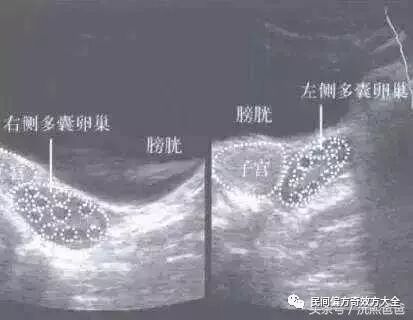

第一个就是:彩超检查。其实,更好的是内(阴)超检查。因为更加清晰地可以看出两侧的卵巢是否呈现多囊的状态。因为多囊卵巢用大白话来说,就是卵泡长不大或者是不排卵,在卵巢上集聚在一起,使得卵巢越来越大,彩超检查的时候,卵巢有超过十个以上的小卵泡就可以确证为多囊。

2. 彩超检查直接确诊多囊卵巢。